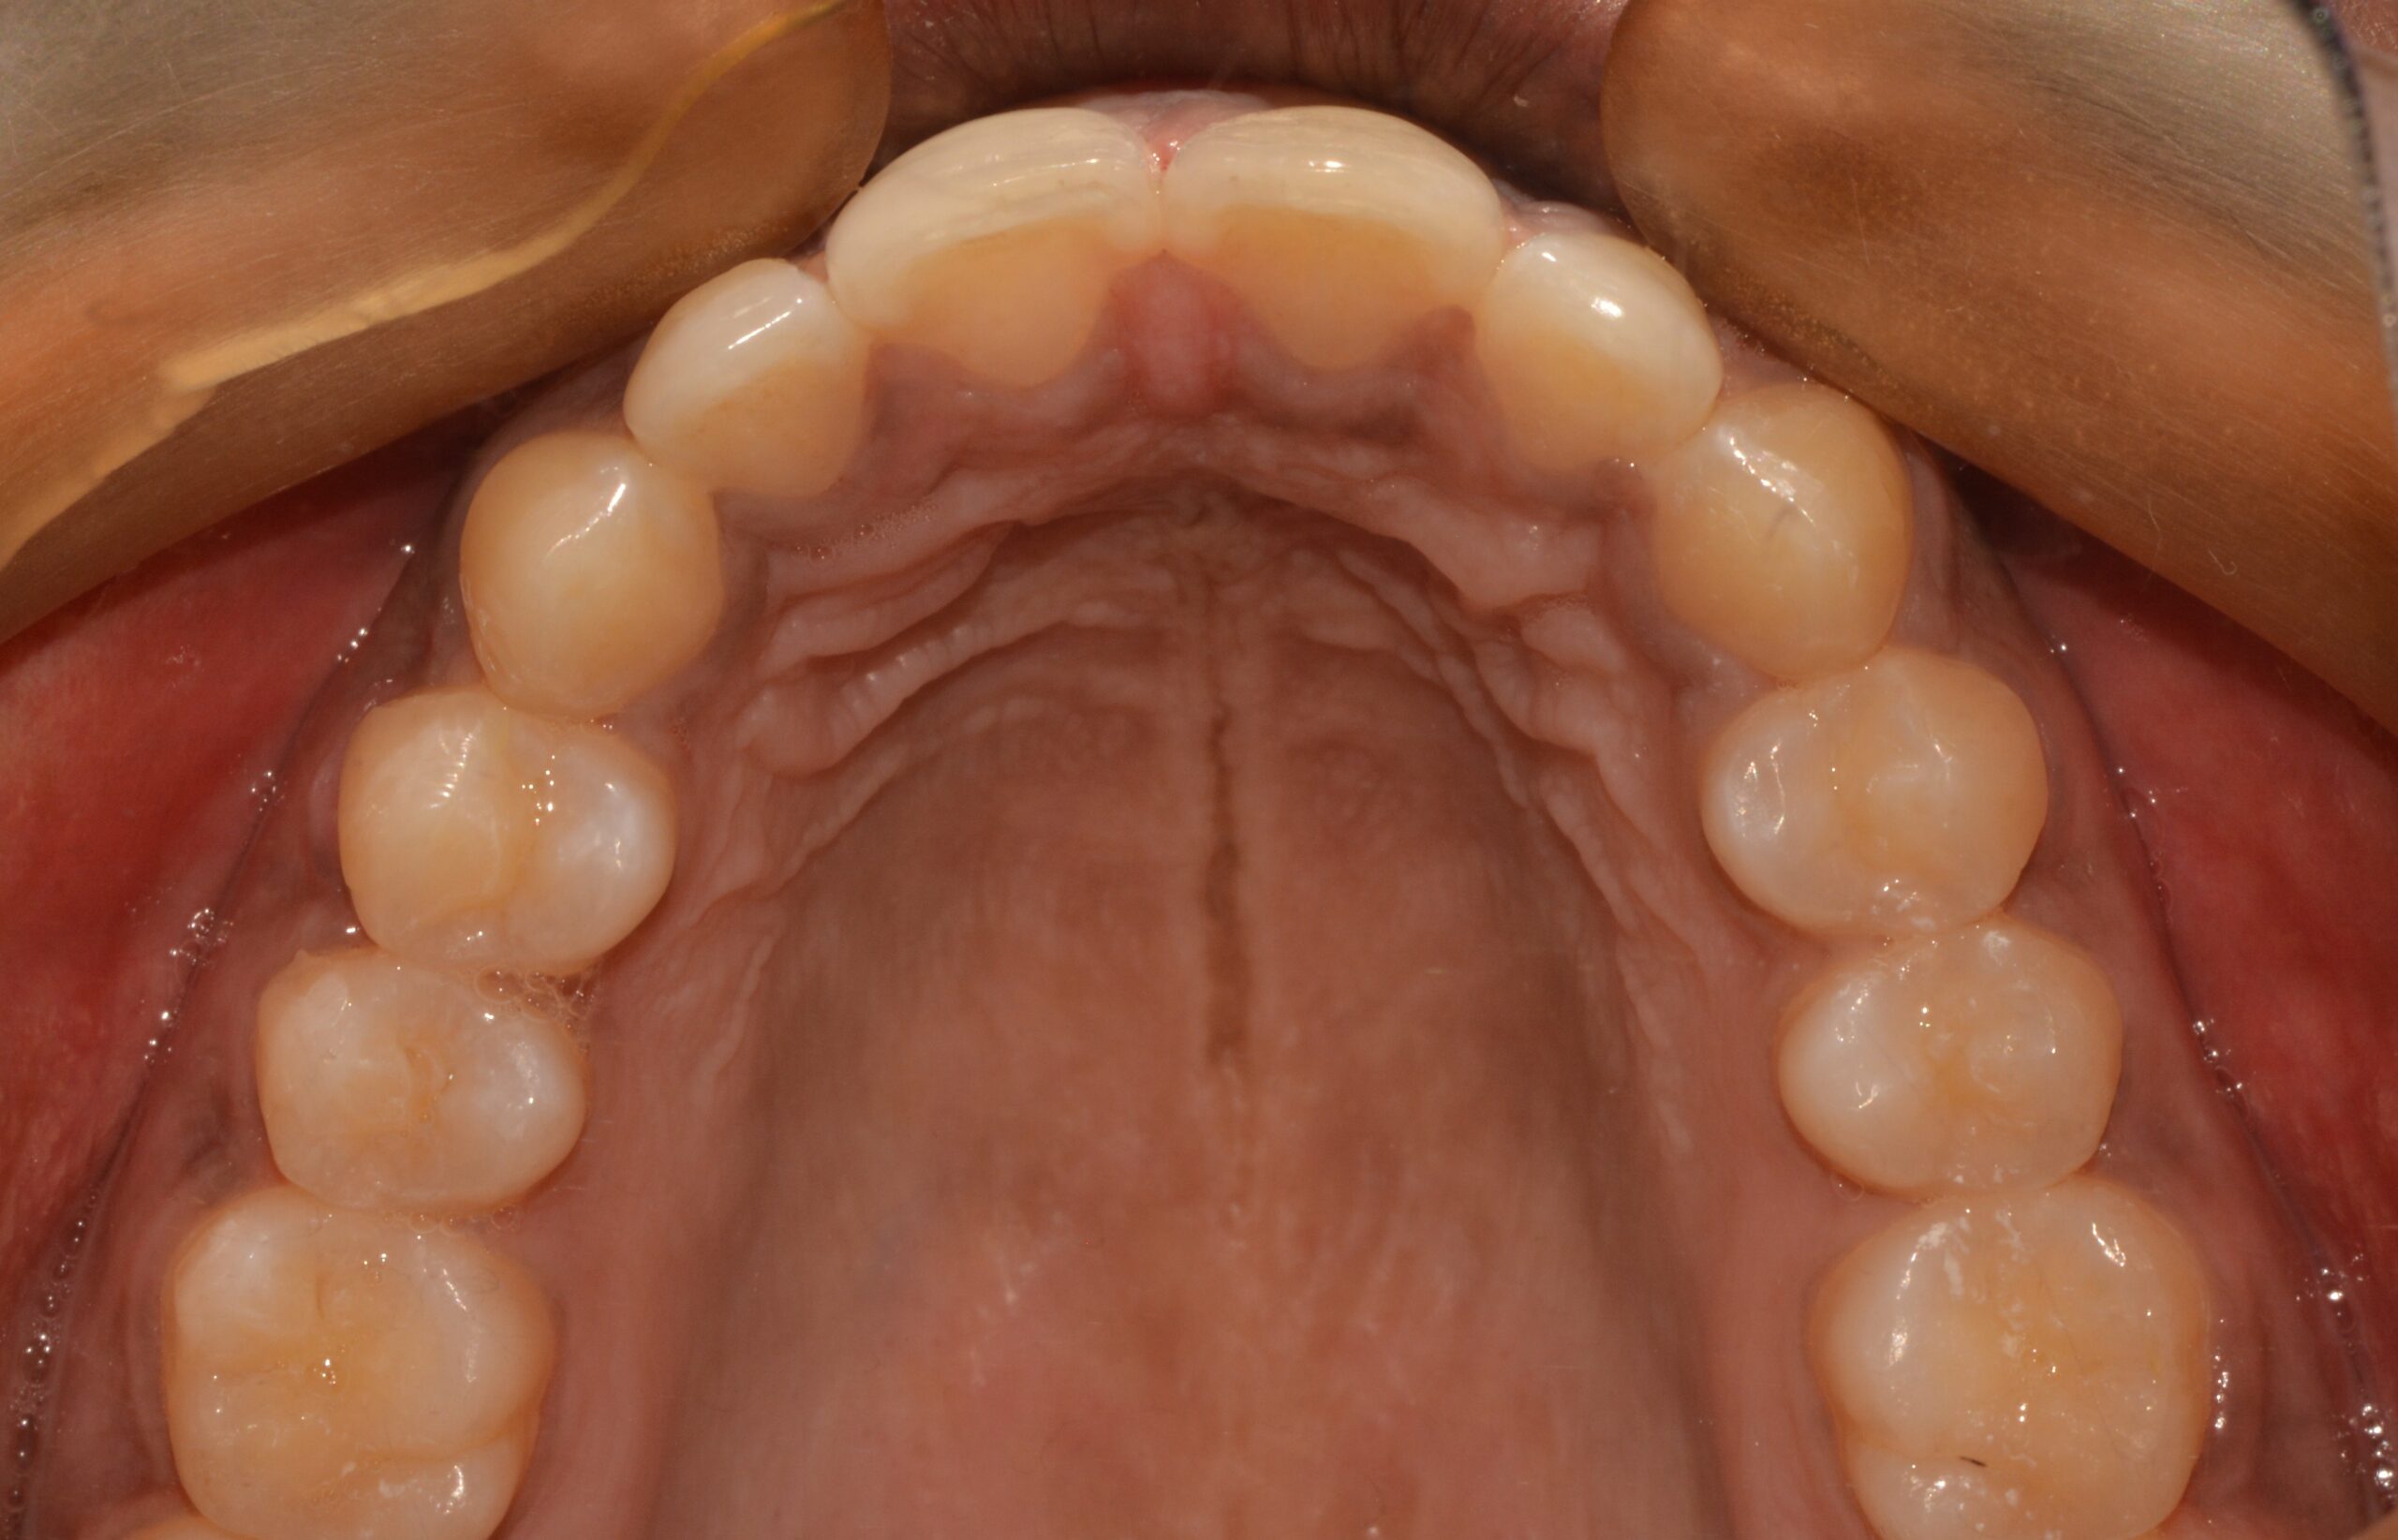

The patient was treated with aligner therapy using Invisalign aligners, which applied light forces to close the gaps. This treatment also helped the loose lower front teeth become stable over time, preventing the need for tooth removal and future implants.

The total treatment duration was between 18 to 20 months.

Before

After